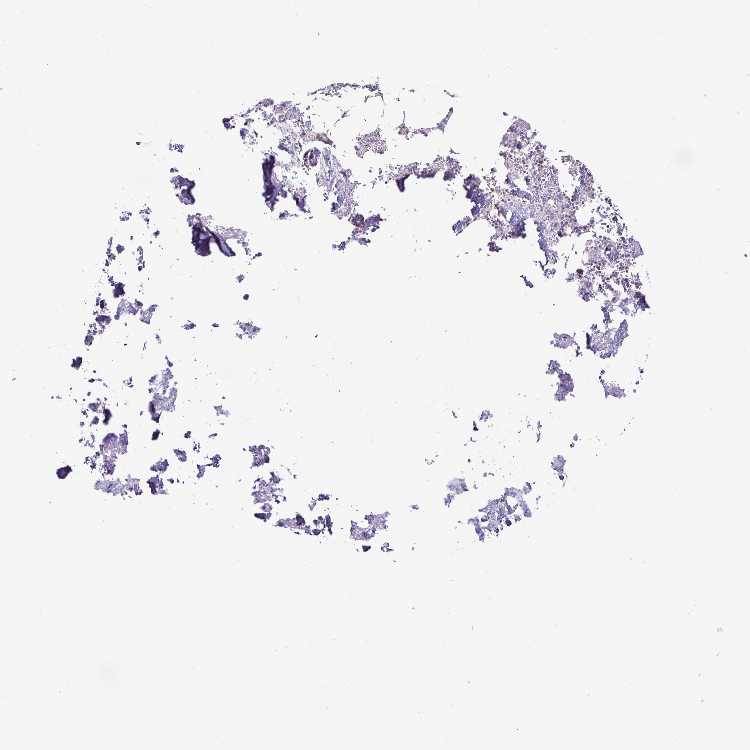

BONE MARROW - Antibody stainingi

Antibody staining in the annotated cell types in the current human tissue is reported as not detected, low, medium, or high, based on conventional immunohistochemistry profiling in selected tissues. This score is based on the combination of the staining intensity and fraction of stained cells.

Each image is clickable and will lead to virtual microscopy that enables deeper exploration of all samples and also displays staining intensity scores, fraction scores and subcellular localization as well as patient and tissue information for each sample.

Antibody HPA054437Antibody HPA058511Antibody CAB015122

Hematopoietic cells Not detectedNot detectedHigh